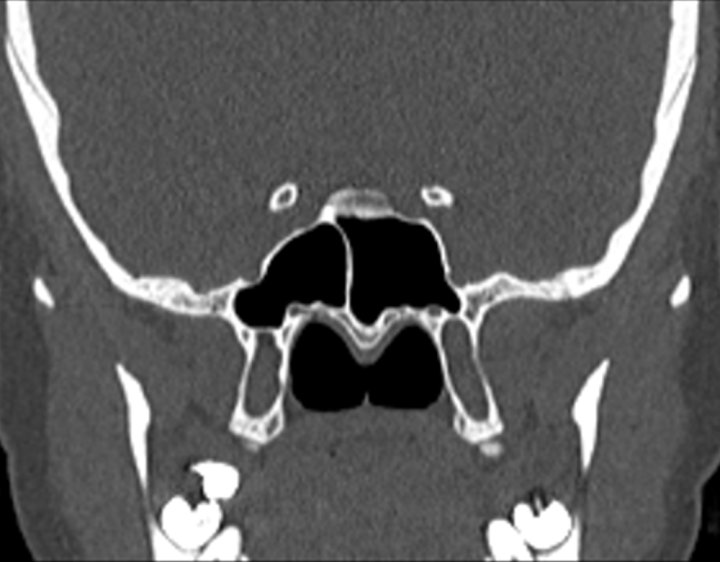

001